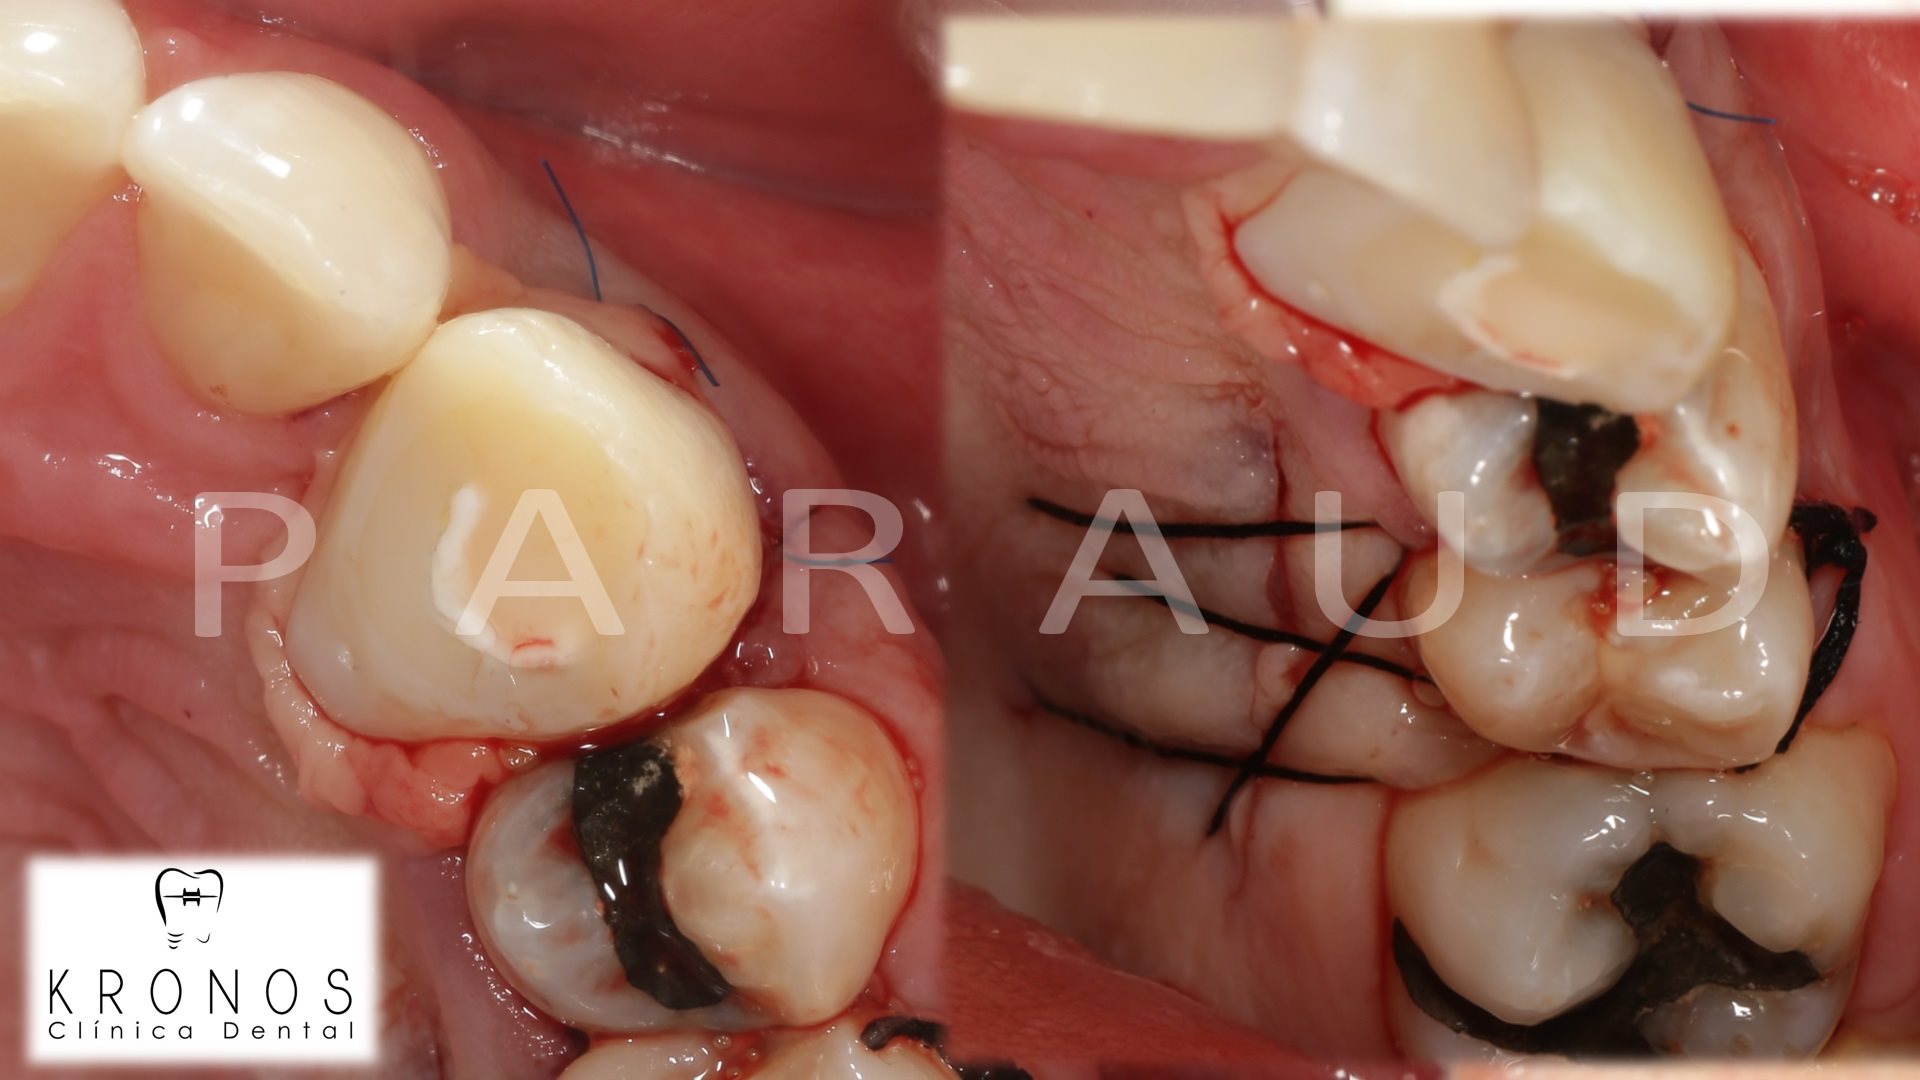

Clinical case: Extraction, immediate implant placement, & provisionalization

- Courtesy of Dr. Iulian Filipov, Romania -

AnyRidge, R2GATE, guided surgery, immediate placement, immediate provisionalization, initial stability, Dr. Iulian Filipov, #25, maxillary posterior, immediate loading, Mega ISQ

AnyRidge implant system, R2GATE, MEGA ISQ, Digital prosthesis

How can primary stability be increased?

Primary stability is especially important in the case of poor quality bone. The instability of dental implants results in fibrous encapsulation and failed osseointegration (Lioubavina-Hack, et al. 2006). One method for increasing primary stability is modifying the surgical technique for implant placement. Studies have reported that the undersized surgical technique, which uses a final drill diameter smaller than the diameter of the implant, results in a higher primary stability when compared with the press-fit technique (Tabassum, et al. 2009, Tabassum, et al. 2010a).